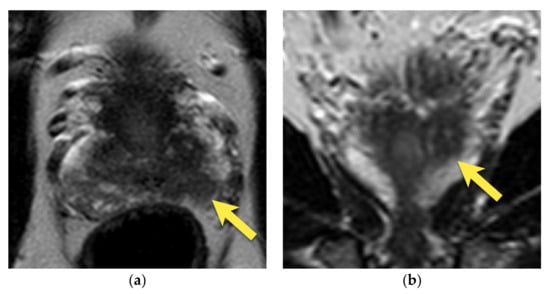

10. Prostatic Abscess